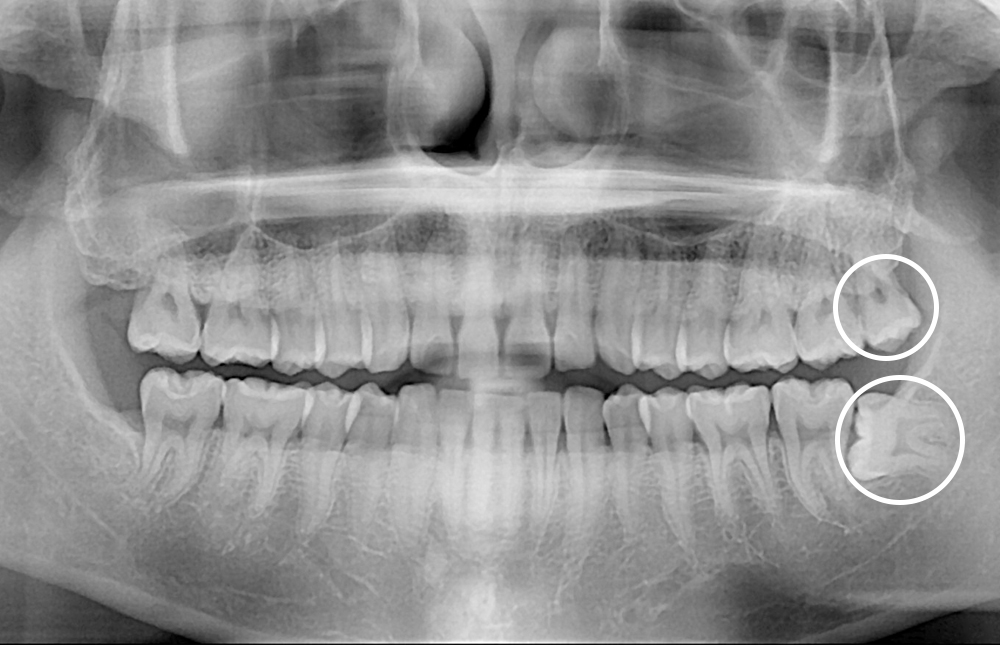

[사랑니] 매복 사랑니 발치

치료전 : 2017-11-20